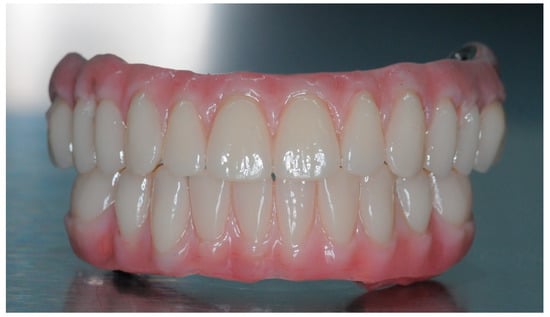

2.5. Final Prosthesis